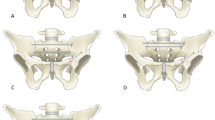

Prior to preparation and biomechanical testing, the specimens were thawed at room temperature for 24 h. Tissue dissection of skin and muscles was done carefully and all ligaments were preserved. After dissection, a fragility fracture of the pelvis (FFP) type IIc was simulated by means of osteotomies using a 1.47 mm oscillating surgical saw [18]. Therefore, the sacrum was cut between the SI-Joint and the neuroforamina in the sacral ala creating a vertical paraforaminal sacrum fracture in zone 1 after Denis classification [19]. Subsequently, the superior and inferior pubic rami were cut approximately 3 cm laterally from the symphysis to discontinue the force transmission to the contralateral hemipelvis site through the anterior pelvic ring during load application.

Under normal operating conditions, the specimens were reduced and treated with either a navigated SI-screw or TITS using a hybrid operating room which consists of a fixed robotic 3D flatpanel detector (Artis zeego, Siemens Healthineers, Germany) and a navigation system (BrainLab Curve, BrainLab, Germany). This ensured an optimal screw pathway for each pelvis. The fractured sacrum was anatomically reduced together with the superior and inferior pubic rami. Fully threaded self-tapping stainless steel 7.3 mm cannulated screws (DePuy Synthes, Zuchwil, Switzerland) were used with a standard washer for fracture fixation. Screw length was chosen specimen individually and according to the group assignment. Whereas for the SI screw fixation technique, care was taken that the screw tip did not cross the midline, for the TITS fixation technique, the screw tip was aimed to perforate all six cortices and extrude from the contralateral ilium. To create a machine fixation point, the L5-vertebrae was embedded in polymethylmethacrylate (PMMA, SCS-Beracryl D-28, Swiss Composite, Jägenstorf, Switzerland) cylinder, such that with the former oriented vertically, the pelvic tilt measured 45°. The fixation was enhanced with 5.0 mm screws. Finally, optical markers were attached to each side of the sacrum and superior ramus fracture, and to the ilium for motion tracking.